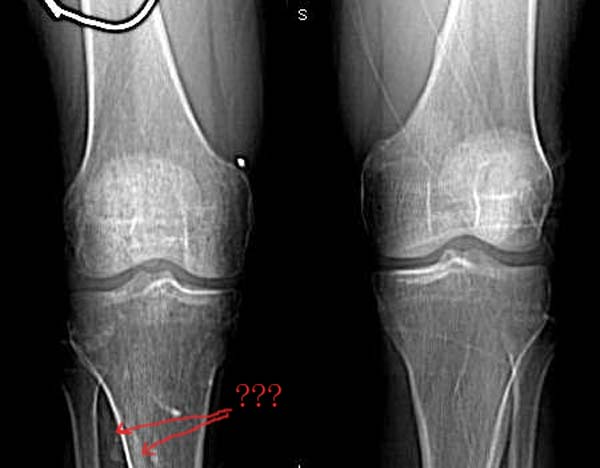

患者,男.40y,右侧膝关节疼痛半年,加重月余

右侧股骨下端 胫骨近端及髌骨见骨质疏松,松质及皮质见虫蚀状溶骨性破坏,皮质变薄,骨小梁减少模糊,胫骨近侧干骺端内侧骨破坏性,关节肿胀,关节间隙增宽,周围未见明显软组织肿块.

临床 右膝关节痛半年,加重月余

考虑 多发性骨髓瘤

1、右膝关节积液是 2、多发性骨髓瘤大于骨质疏松,因为骨质疏松多为全身性,普遍性的。

就膝关节的病变,我还是支持wawaquan版主的意见,病理上可以解释为长期的关节炎性病变,充血引起的骨质疏松!!多发骨髓瘤好发于扁骨,再说,发生于长骨的多为一骨多病灶,象这样关节两端,骨质改变相同的少见!软组织变化也不支持.

建议:1.胫骨全长摄片检查,排除中段病变;2.尿查本周蛋白;

考虑为缺血性改变。股骨远端及胫骨近端均呈同样改变,髓腔及骨皮质均未见骨破坏改变。

无积液,皮质变薄、小梁纤细无中断,骨干变细,周围肌群明显萎缩,不支持mm,也不支持滑膜慢性充血所致骨质疏松,故首先考虑废用性局限性骨质疏松,请结合临床查找疼痛原因。